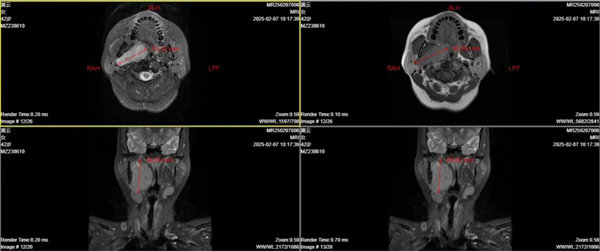

患者黃女士,咽部異物感兩年,嚴重影響日常生活,遂于春節后來我院耳鼻喉科就診。耳鼻喉科副主任醫師章松林為患者查體后輔以磁共振檢查,確定患者右側咽旁間隙存在約6.0cm×4.0cm的巨大腫瘤,建議患者住院行進一步檢查治療。

章松林將患者病情匯報科室主任劉杰、副主任宋國昶,團隊經過討論研究后為患者制定適宜手術方案——經口翼下頜韌帶內側入路右側咽旁間隙巨大腫瘤切除術。手術由章松林主刀,歷時3小時完成,術后患者恢復良好,聲帶活動及吞咽功能均未受影響。